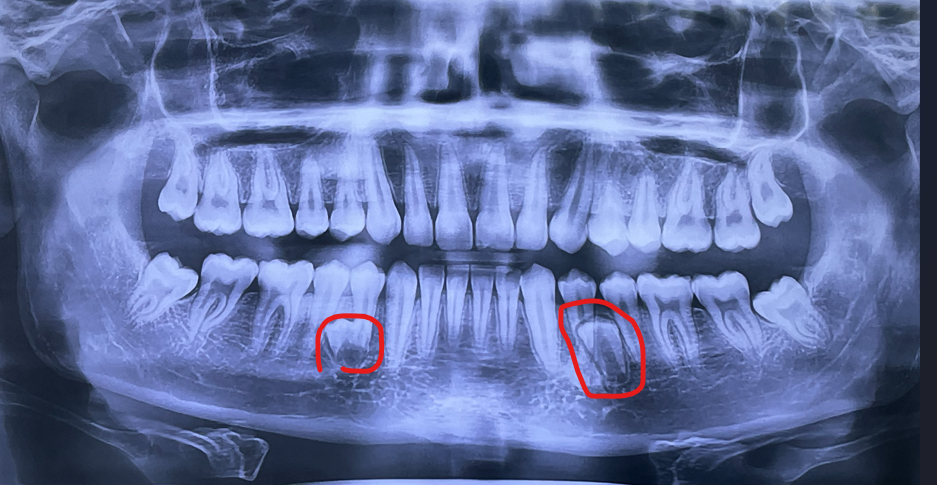

I've always heard the myth that it can change the face shape or recess you or sum shit like that but I never seen research that proves that

I will have them removed in the next 3 months

i have two random teeth that never got out that are just extra too jfl

u got hyperdontia, u will probably have to remove these random teeth aswell